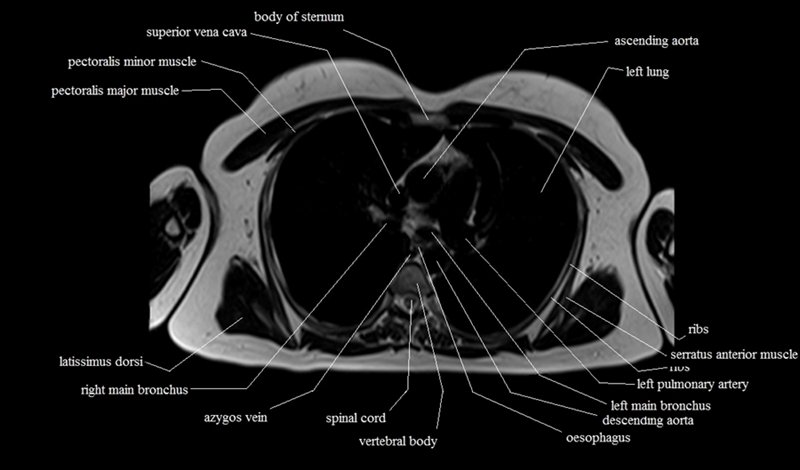

MRI Axial Cross Sectional Anatomy of Chest

This MRI chest (thorax) axial cross sectional anatomy tool is absolutely free to use. Use the mouse scroll wheel to move the images up and down, or alternatively, use the tiny arrows (→) on both sides of the image to navigate through the images. For a more detailed view, double-click the image to view it in full screen, and use the menu in the top right-hand corner to view individual slides or play them in a loop.